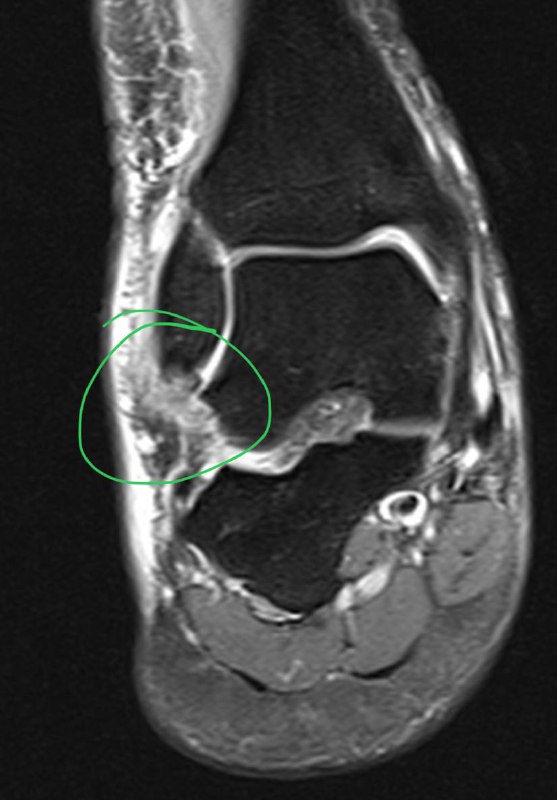

Подборка с рутины. Что видел за последние несколько дней.

Частичный разрыв передней малоберцово-таранной связки.